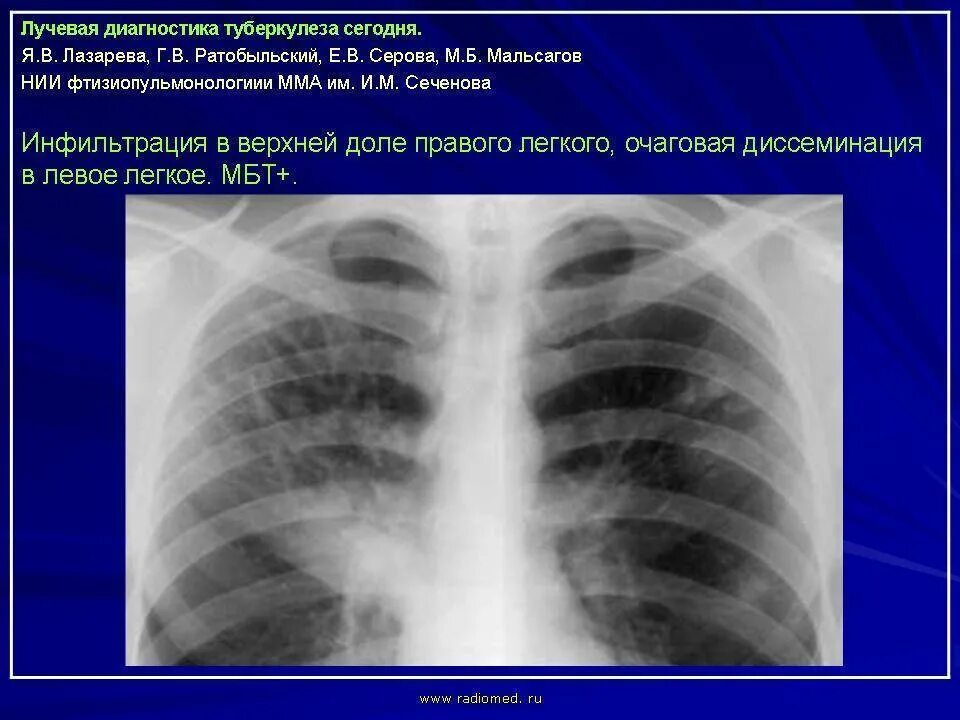

Стадия инфильтрации легких